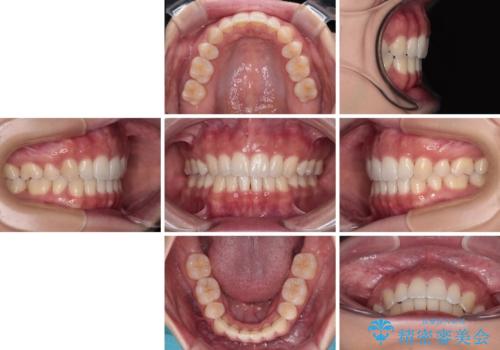

閉じにくい口元をワイヤー抜歯矯正でスッキリした口元に

- 上下前歯の隙間と口元の出っ張った感じを気にして来院された患者様です。

上下の隙間は舌突出癖によるもので、またその癖により前歯が前方に出ている状態でした。

口元の出っ張りを改善するため、上下左右第一小臼歯4本を抜去し、ワイヤー装置にて矯正治療を行うこととしました。

舌の突出癖を改善するためのトレーニングをしっかりと行っていただいたことで、比較的スムーズに治療を進めることができました。

口元の突出感もしっかりと改善することができました。